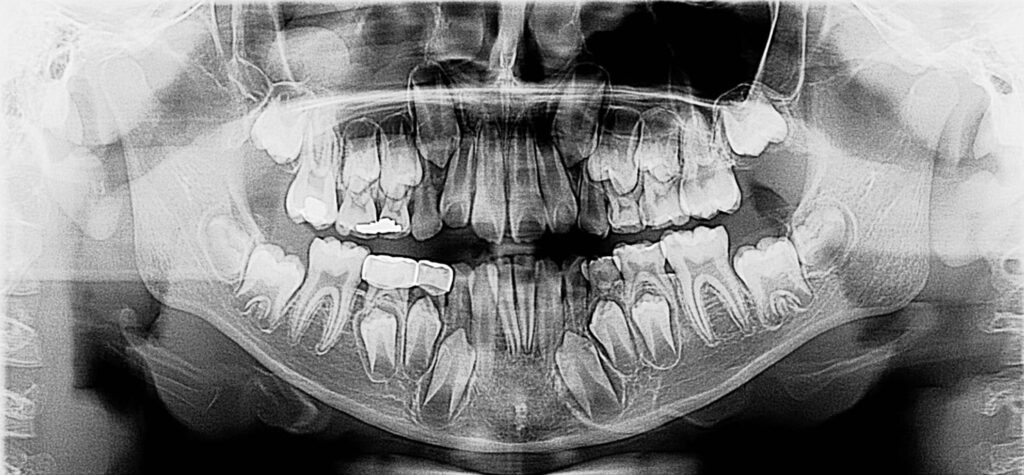

7-year-old boy with radiographic finding

A 7-year-old boy with an unusual finding on a panoramic film.